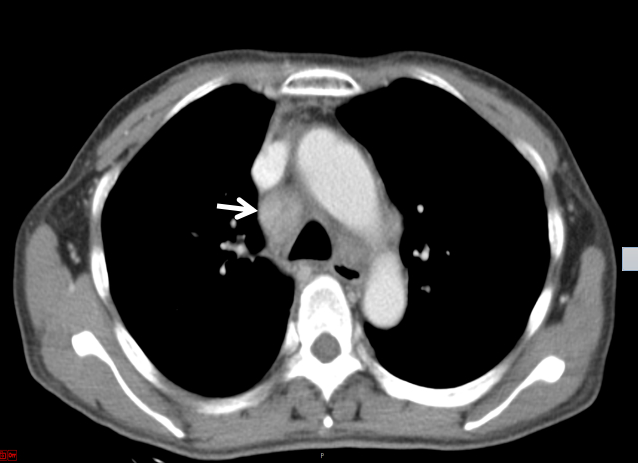

后再因“反复发热、多关节痛7月、皮疹3月”于2019-09-17入住本院风湿科。入院当天体温36.5℃,心率106次/min,呼吸20次/min,血压118/75 mmHg。步态正常,自主体位。左颈部肿大淋巴结。四肢和背部可见紫癜样皮疹,按压部分褪色,伴抓痕。腹软,肝脾未及。图 2为2019-09-21胸部CT结果,箭头所指为肿大淋巴结。

| 图 2 胸部CT示纵膈淋巴结改变 |